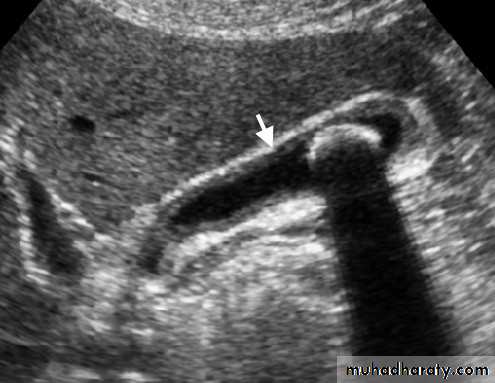

Gall bladder ,biliary tree

CBD not > 7mmnormal intrahepatic tree is too small to seen

• no contrast.Gall stone & cholecystitis

Obstructive jaundice

US